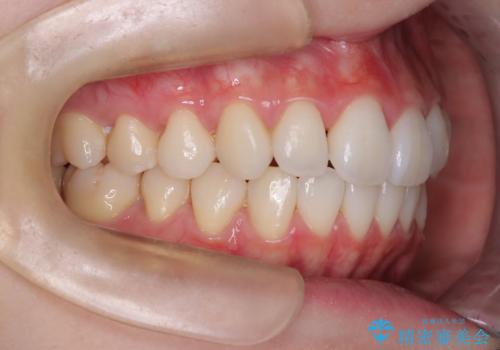

- 前歯の凸凹を主訴に来院されました。

スペースを作るために顎間ゴムを使用して、奥歯の遠心移動をおこない配列しました。

奥歯の遠心移動を行うことで、犬歯関係も良い状態に仕上げることができました。